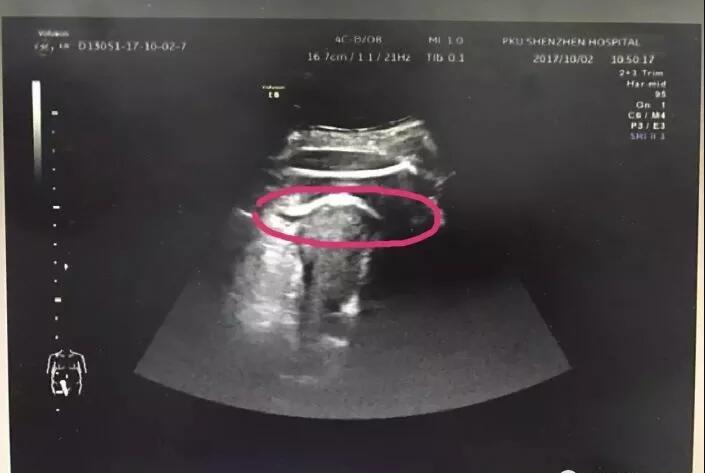

医生初步怀疑患者子宫破裂,当即安排做了B超。检查发现,胎儿的一条腿“踢破”了子宫,进入了腹腔,大腿根正卡在子宫壁上!

红色圆圈处是胎儿的腿,已经伸到子宫壁外